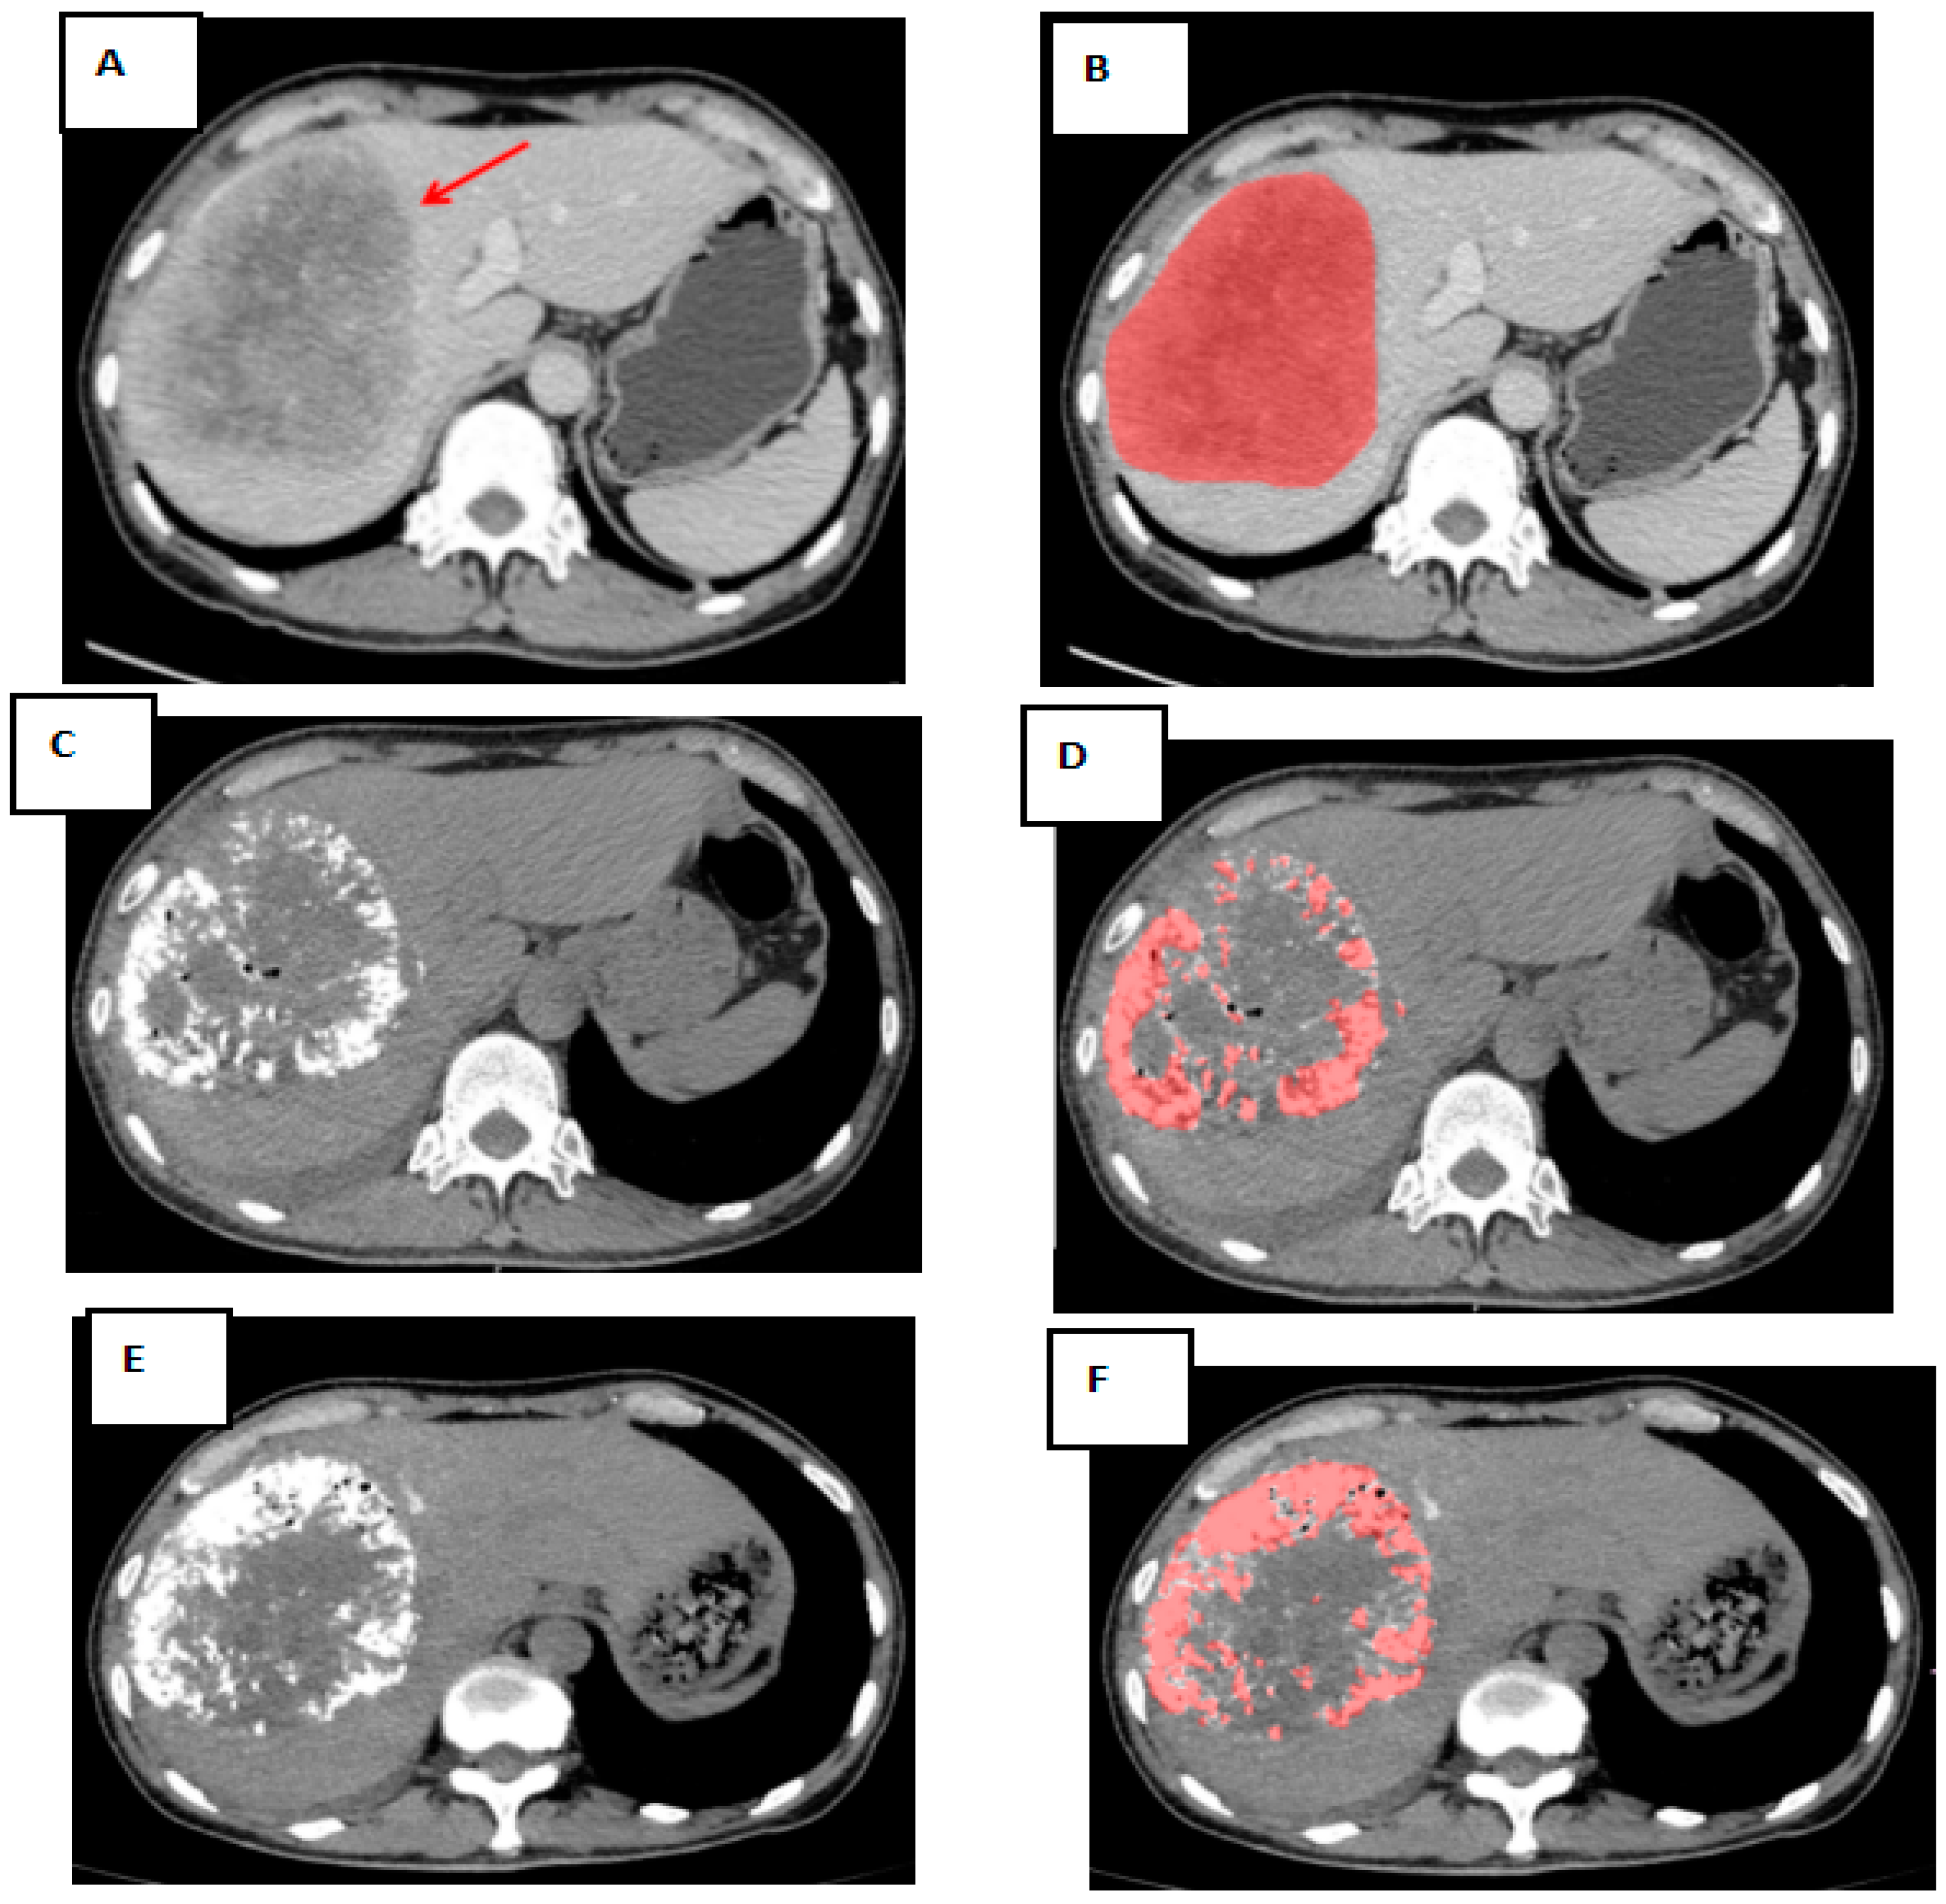

2.3. Quantification of Volumetric Oil Deposition